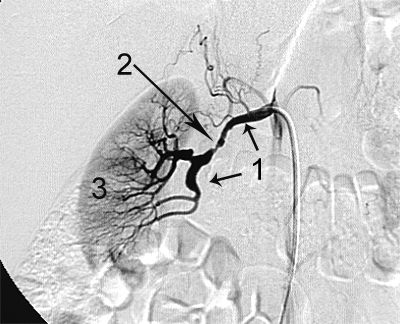

Приклади ангіограм:

стеноз правої ниркової артерії    пухлина підшлункової залози

Артерії: загальна печінкова(1),

праві печінкові (2), ліва печінкова (3),

селезінкова (4), пухлина підшлункової залози (5).